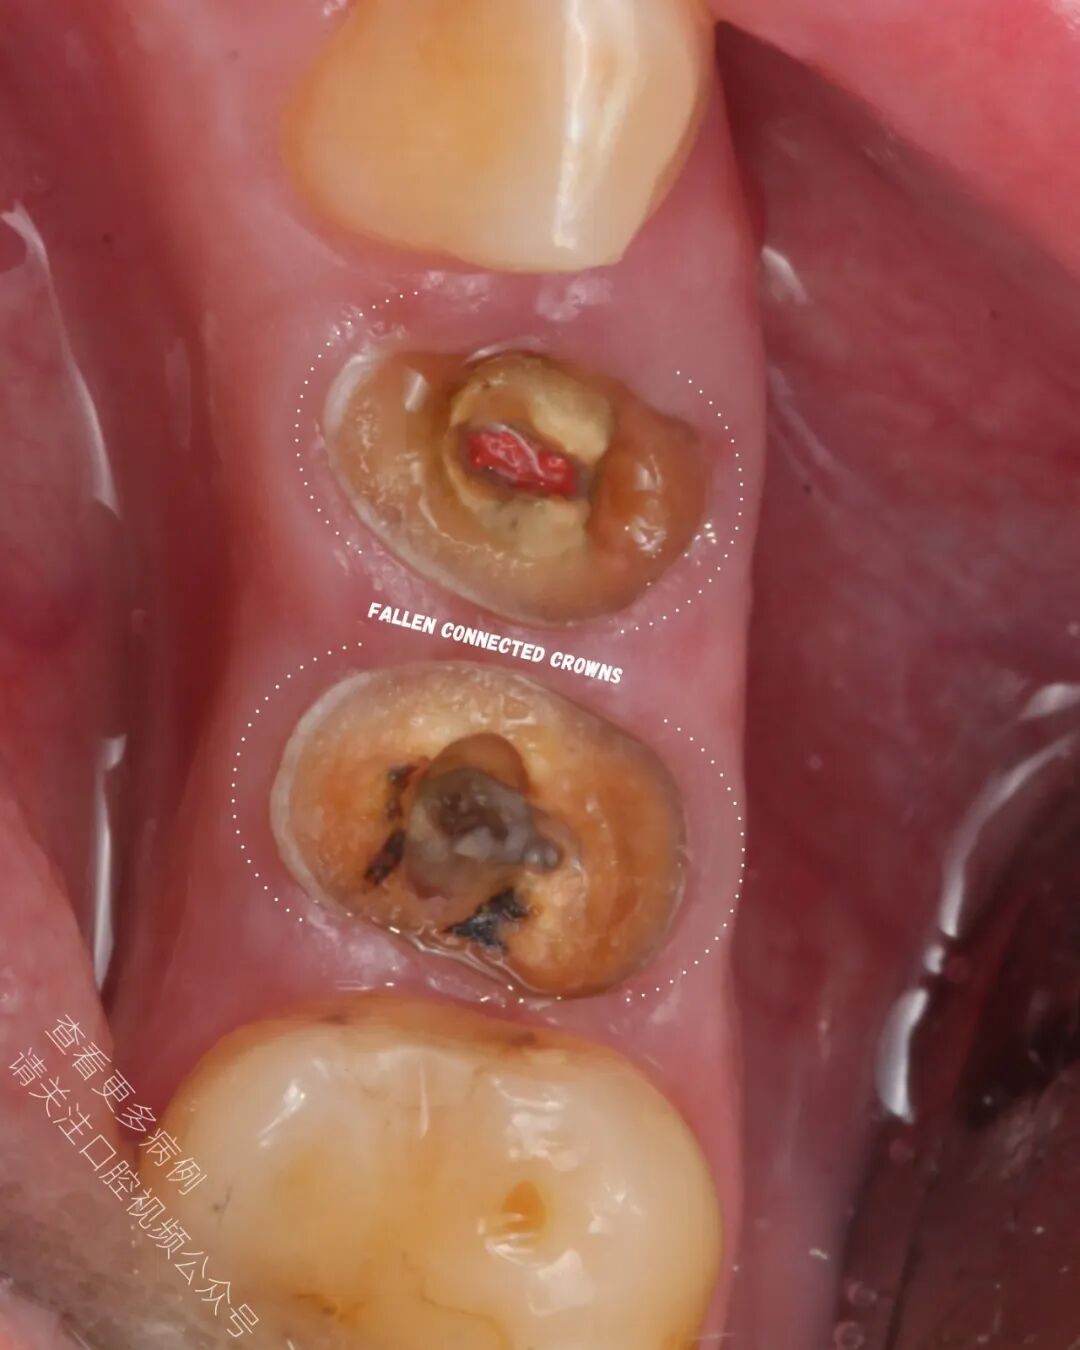

从深龋坏到完成全冠修复——给这些牙齿最后一次重生的机会。

🪄 患者希望尽可能保留牙齿,于是我们达成一致

🪄 成功使用橡皮障隔离,对两颗前磨牙进行了再根管治疗(ReRCT)